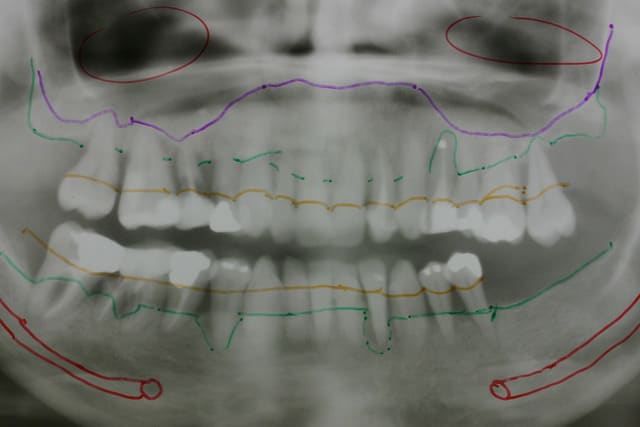

Implantations à venir les enfants ....

Il s agit de 2 femmes et un homme.

Le monsieur a vu son traitement commencer par un complet du haut amovible le tps que les PRFs me comblent un peu les zones paro +++ et le tps de qques séances d ostéotension

On commencera par poser en bas en enfoui, des disk en zone molaires car très étroit et peu haut

Les 2 dames sont encore ds l expectative mais il est urgent de prendre une décision vu l état paro très avancé. Une de 40 à peine et la seconde de 50 ans... 20 années de tabagisme pour chacune...